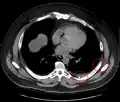

Fracture de côte sur un scanner thoracique Fracture de côte sur un scanner thoracique